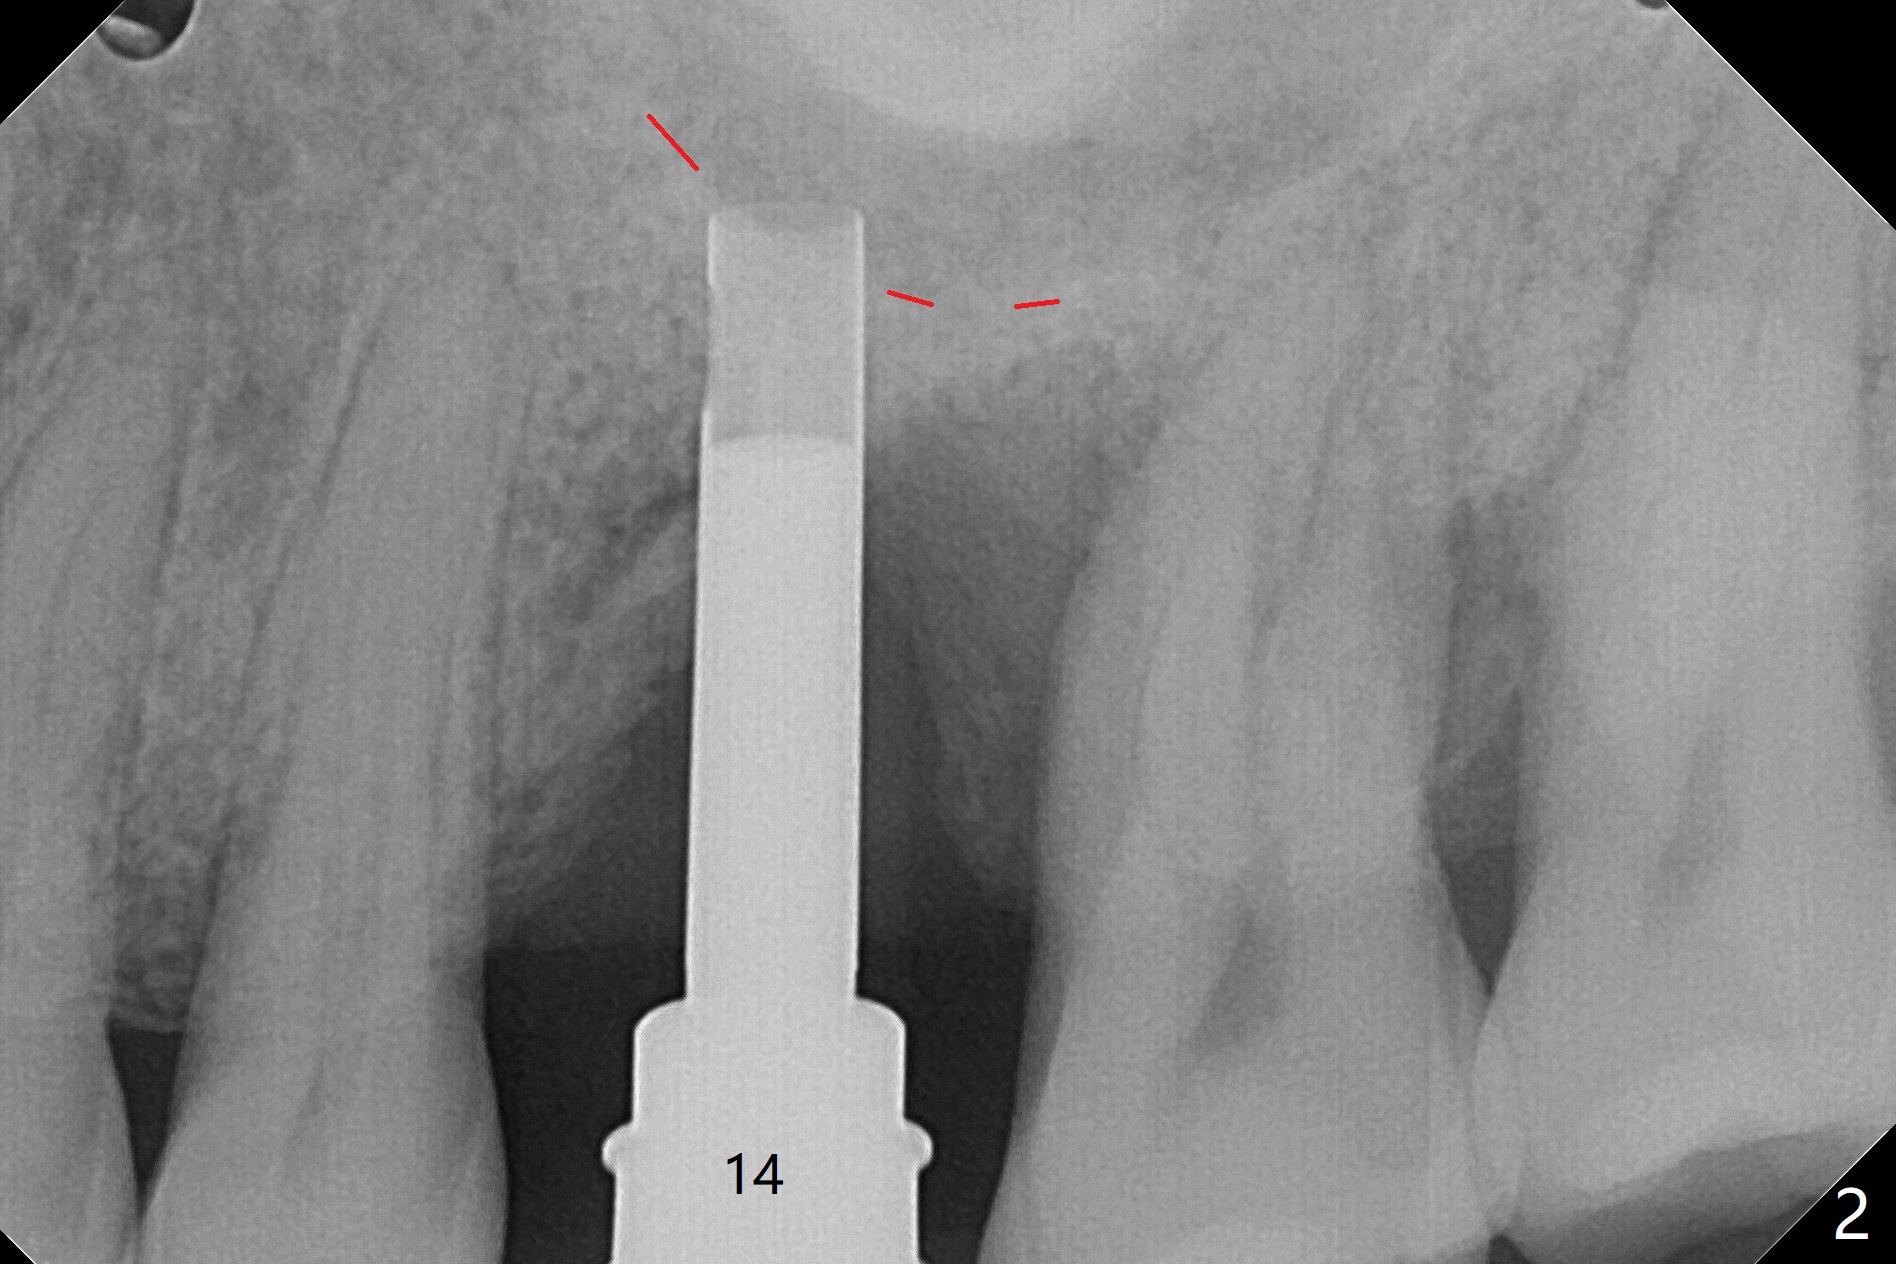

切开,使用导板完成初步钻洞,然后应用特殊上颌窦提升骨凿,顶端象环形刀,两侧有锥形刀刃(图一:箭头,防止骨凿突然进入上颌窦),由于窦底硬,骨凿并没有完全提升窦底(图二:红虚线)。使用短一号植体(图三),恰好进入上颌窦(没有骨粉),利用植体和基台固定骨粉(图四:*),覆盖两张PRF膜,将两侧厚的粘骨膜瓣尽量靠拢(图五)。最后树脂敷料。术后八天病人抱怨伤口和邻牙疼痛,骨粉被水牙线冲出来,进行邻牙咬合调整,疼痛即刻减轻(图六),再服用抗生素一周。一周后仍有轻度不适,局部牙龈正常,没有触痛。No Caries Magic Sinus Lifter 提升 Xin Wei, DDS, PhD, MS 1st edition 04/02/2021, last revision 04/18/2021